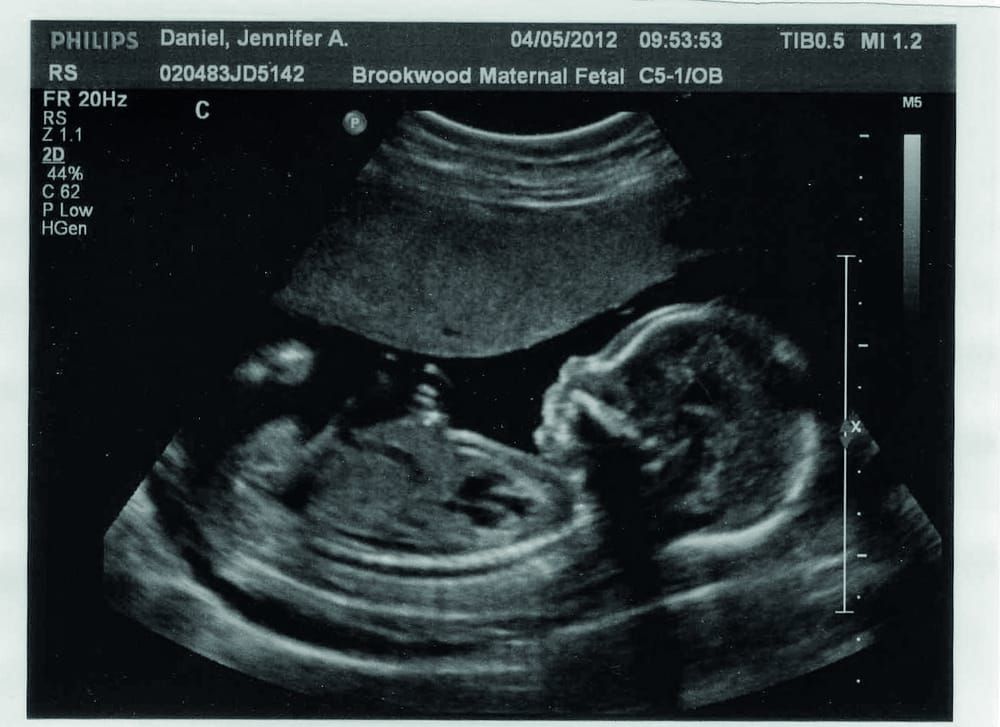

Lauren Ratcliffe reports on a trail revealing the most effective pre-natal monitoring technique

During some pregnancies, abnormal blood flow from the placenta can deprive the foetus of sufficient oxygen and nutrients to grow to its full potential. This condition is known as foetal growth restriction and affects up to 8% of all pregnancies, a total of 60,000 babies per year in Europe and the USA. The condition is associated with an increased risk of stillborn birth, neonatal death and neurological and cardiovascular disorders later in life. When diagnosed, doctors sometimes decide to deliver these babies early, before the lack of oxygen and increased acidity becomes too damaging. However, this can be a tricky decision to make and involves balancing the risks of keeping the baby in a poor womb environment with the increased risk of morta that’s associated with premature births.

Currently, there is no consensus for when to trigger the delivery in mothers of babies with foetal growth restriction and no best form of monitoring to inform this decision. The Trial of Randomised Umbilical and Foetal Flow in Europe (TRUFFLE) aimed to help clarify this decision by investigating which of the current monitoring methods are most effective in reducing pre and post-natal problems associated with foetal growth restriction.

Early ductus venosus changes - this uses ultrasound to monitor the resistance in blood flow within the ductus venosus, a small vessel below the fetus’ heart, and gives an indication of oxygen shortage.

Late ductus venosus changes - this also uses ultrasound to monitor variability in the waveform of the blood flow in the ductus venosus and indicates abnormalities in the foetus’ heart contractions.